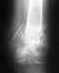

Re: ложный сустав верхней трети б/берцовой кости голени на правой ноге

Может быть, можно и вовсе без трансплантата - но снимка-то нет, поэтому ничего определенного не сказать.